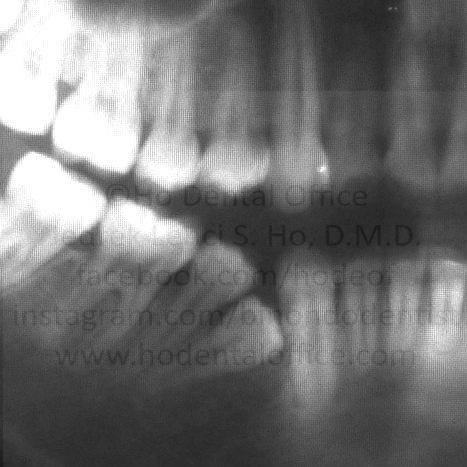

supernumerary teeth (teeth beyond the normal 38 teeth in adulthood)

- mesiodens - literally means a tooth in the middle

- supernumerary incisor, premolar, or canine

- Supernumerary teeth literally are just a waste of space. They can only be considered "useful" if they are orthodontically aligned to replace a badly decayed tooth located above/below them.

Since they are impacted, they have no function and only take up space in the mouth. They are also usually discovered via dental x-rays, so having a dental check-up with x-ray examination done during the early teenage years are important in order to avert possible complications in the future.